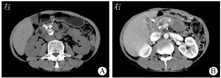

于2019年8月7日急诊行腹腔动脉造影+脾动脉瘤栓塞术(图3),术中经右侧股动脉穿刺置管后,引入5 F Corba导管行腹腔干造影,见脾动脉一条分支中段造影剂外漏,形成假性动脉瘤。经微导管超选择脾动脉出血分支,于破口远端和近端分别予6 mm×2 mm弹簧圈各2枚栓塞,复查造影栓塞满意。最后经Corba导管行腹腔干造影未见明显造影剂外渗,弹簧圈均在位。术后静脉滴注奥美拉唑40 mg(1次/d)抑酸护胃,加贝酯300 mg(1次/d)静脉滴注抑制胰酶活性。患者全身营养状况显著改善后,于2020年10月13日行全身麻醉下胰管切开取石+胰管-空肠吻合+广泛肠粘连松解术,术中见胰腺组织明显萎缩,质地硬,胰尾和脾周致密粘连,胰体尾部假性囊肿与周围组织紧密粘连难以剥离,且易出血。于胰腺表面纵行切开至胰管,沿主胰管纵行切开约5 cm,取出其内结石。取距离十二指肠悬韧带远端约25 cm处空肠,经结肠后方,以可吸收缝线行胰管-空肠侧侧吻合。取距离胰肠吻合口远端约50 cm处空肠,与胰肠吻合口近端空肠行空肠-空肠侧侧吻合。丝线扎闭胰肠吻合口近端肠段,完成非离断式(uncut) Roux-en-Y吻合。2020年10月16日上腹部CT平扫加增强扫描检查(图4)可见胰腺头颈部和部分体部多发点状高密度影,胰腺尾部可见金属伪影,增强扫描无明显强化,周围见部分渗出。术后予以醋酸奥曲肽注射液抑制胰腺分泌,并行窦道造影后以0.9%氯化钠溶液反复冲洗引流管,2周后患者引流液明显减少,无发热、畏寒等不适,予以出院。患者出院后定期复查,胰腺假性囊肿持续置管引流,每日引流约20 mL淡黄色透明液体。2021年3月28日起患者胰腺假性囊肿引流液呈乳糜样(图5),每日引流量为20~30 mL,无畏寒、发热。

消化内科谢渭芬主任医师:该患者目前存在2个问题,一是胰腺假性囊肿经久不愈,二是假性囊肿引流出乳糜样液体。首先,该患者虽然通过外科手术行主胰管切开取石,完成胰管-空肠吻合术解除主胰管结石梗阻,但考虑到囊肿较大,可能包绕部分分支胰管,且胰管被结石阻塞导致胰管压力升高,当分支胰管压力高于囊内压力时,部分胰液仍无法通过胰肠吻合口进入肠腔而潴留于囊内,导致假性囊肿不能愈合。其次,此次复诊发现患者出现乳糜样囊液,根据引流液乳糜试验阳性,可确定为假性囊肿内出现乳糜漏。乳糜漏为胸导管或淋巴管主要分支发生破损导致乳糜液漏出,腹腔乳糜漏常见于腹部外科手术后,特别是胰腺手术和结肠手术淋巴结清扫后2~3 d,但该患者术后短期内腹腔和假性囊肿引流液均未出现乳糜样改变,此次出现乳糜漏为术后6个月,考虑与手术无关。胰腺炎后乳糜漏非常罕见,胰腺假性囊肿内合并乳糜漏鲜有文献报道。本例患者假性囊肿内出现乳糜漏,其一考虑假性囊肿内的囊液侵蚀淋巴管导致乳糜液漏入囊肿中所致;其二考虑该患者病程较长,反复出现慢性胰腺炎急性发作,胰周渗出长期压迫淋巴管致淋巴回流不畅,远侧淋巴管扩张,最终导致淋巴管破裂至囊内引起乳糜漏。后续治疗中给予醋酸奥曲肽注射液抑制胰腺外分泌、0.9%氯化钠溶液冲洗囊肿,治疗有效,亦证实上述推测。

胰腺炎后乳糜漏非常罕见,目前尚未见胰腺假性囊肿内出现乳糜漏的文献报道。本例患者乳糜性囊液出现的原因主要考虑为术后假性囊肿侵及淋巴管,以及长期胰周炎性渗出压迫周围淋巴管导致淋巴管阻塞,远端淋巴管压力增大破裂,从而导致乳糜漏。